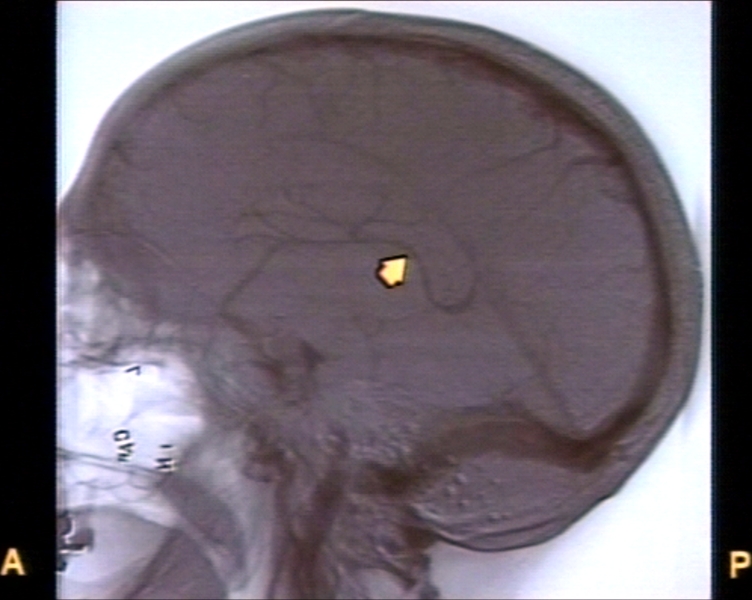

RADIOLOGY: VESSELS: VASCULAR: CARDIOVASCULAR: VEIN: INTERNAL CEREBRAL VEIN (ANGIOGRAM)